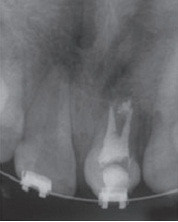

女,十岁,单侧唇腭裂致21牙、22、12牙畸形,且21牙、22牙间牙槽骨发育不全。经自体髂嵴骨移植后,拔除21牙、22牙行正畸治疗以将23牙移动至22牙位置。同时将正畸需拔除的下颌第一前磨牙移植到21牙的牙槽窝内。并在正畸治疗结束后树脂恢复21牙、22牙形态。患者18岁时拔除左上颌乳尖牙行种植义齿修复。